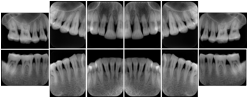

Intra-oral radiography typically involves acquisition of multiple images of various parts of the dentition. Many digital radiographic systems offer customized templates that are used for displaying the images in a study on the screen. These templates may also be referred to as mounts or view sets. The Structured Display Object represents a standard method of encoding and exchanging the layout and intended display of Structured Displays. A structured display object created in this manner could be stored with a study and exchanged with images to allow for complete reproduction of the original exam.

In most standard cases, images are oriented in structured layouts. These structured displays are useful to be shared between providers for reference purposes.